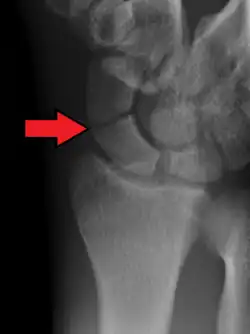

| An X-ray showing a fracture through the waist of the scaphoid | |

Scaphoid fractures are often diagnosed using plain radiographs and multiple views are obtained as standard.[9] However, not all fractures are apparent initially.[7] In 1/4 of cases, the clinical examination suggests a fracture, but the X-ray does not show it, even though there is indeed a fracture.[10] Therefore, people with tenderness over the scaphoid (those who exhibit pain to pressure in the anatomic snuff box) are often splinted in a thumb spica for 7–10 days at which point a second set of X-rays is taken.[7] If a minimally displaced fracture was present initially, healing will now be apparent. Even then a fracture may not be apparent. A CT Scan can then be used to evaluate the scaphoid with greater resolution. The use of MRI, if available, is preferred over CT and can give one an immediate diagnosis.[11] Bone scintigraphy is also an effective method for diagnosis fracture which do not appear on Xray.[12]

A subtle scaphoid fracture -

A more obvious scaphoid fracture on a scaphoid view X ray -

Radiolucency around a 12 days old scaphoid fracture that was initially barely visible.[13]